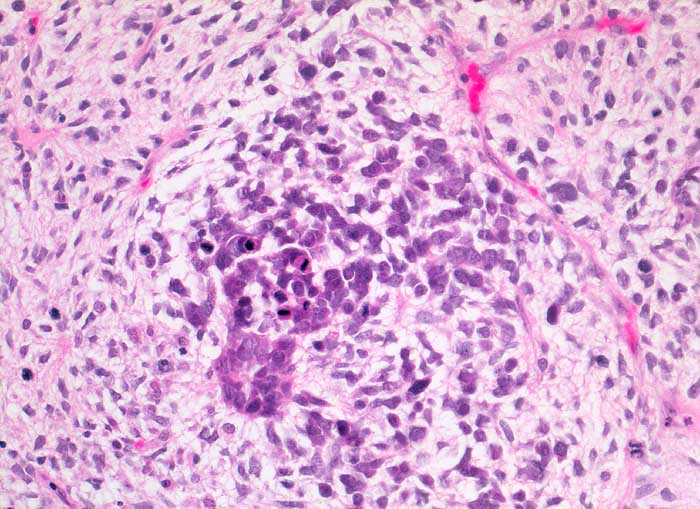

Müllersche Mischtumoren bestehen aus einer epithelialen und einer mesenchymalen Komponente. Die epitheliale Komponente ist in der Regel ein Adenokarzinom. Die Sarkomkomponente kann homolog (Leiomyosarkom, Stromasarkom, Fibrosarkom) oder heterolog (Rhabdomyosarkom, Chondrosarkom...) sein also nicht aus ortsständigem Mesenchym entstammend. Am häufigsten treten diese Tumoren im Uteruscavum auf. Sie können aber auch in anderen Lokalisationen des Genitaltrakts vorkommen. Die Ausstriche enthalten ein buntes Zellbild mit deutlich atypischen Zellen. Wenn neben Karzinomzellen auch atypische mesenchymale Zellen vorhanden sind, kann zytologisch die Diagnose eines malignen Müllerschen Mischtumors gestellt werden.